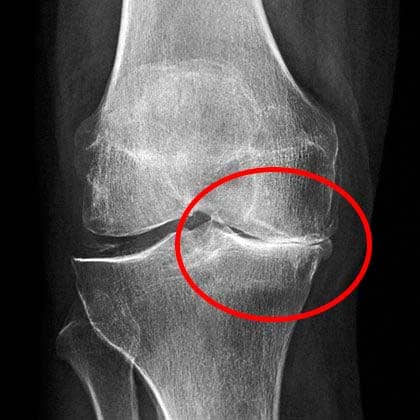

หมอดูฟิล์ม X-ray นานหน่อย แล้วบอกว่าฉันควรหลีกเลี่ยงการยกของหนักหรือทำงานหนัก ไม่ควรยกของหนักเกิน 2 กิโลกรัม!

ผลการตรวจแสดงให้เห็นว่าข้อเข่าของฉันมีปัญหาร้ายแรง